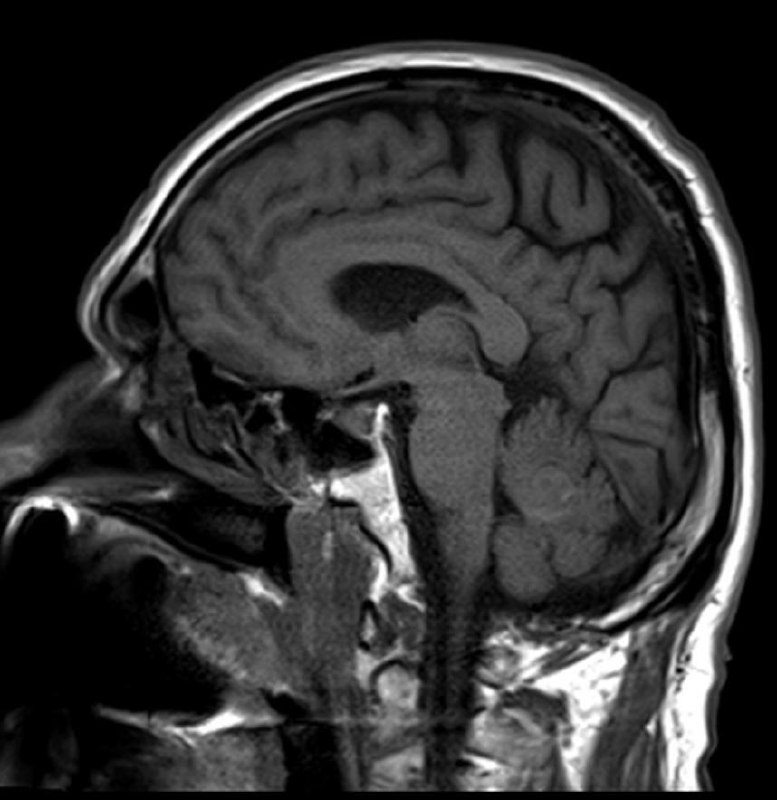

в декабре 2020 удалена менингиома, а теперь - вот так